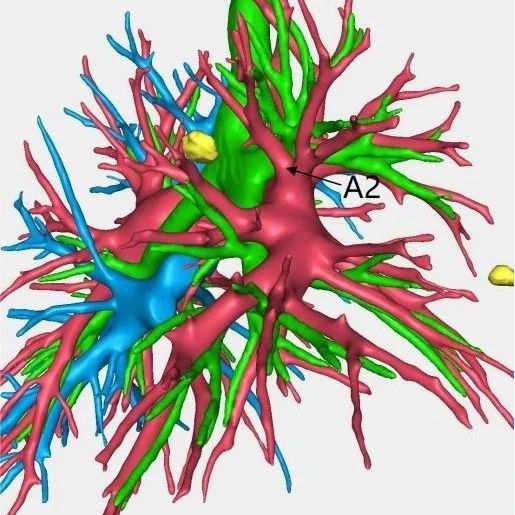

患者林女士今年65岁,长期旅居国外的她在回国后常规体检时查出右肺有2个高危的磨玻璃结节,慕名找到我院胸部肿瘤外科方卫民主任医师。医生团队详细分析了患者的肺部CT及三维重建结果,发现2个结节分别位于右上肺后段边缘及右中肺叶中央,如果直接采用手术切除的方法,要多切除整个右肺中叶,将损失较多的正常肺组织,影响生活质量,得不偿失。

三维重建结果

由于患者签证时间将到,无法分次手术,医生团队经过反复讨论,最终为患者量身定做了“针孔消融+单孔微创”的杂交手术方案。首先在医院肿瘤与血管微创介入治疗中心CT引导下为患者右中肺叶结节进行热消融治疗,仅仅一个针眼;接着进行单孔胸腔镜亚肺段切除,仅仅一个3cm大小的切口,术中冰冻病理报告:原位腺癌,疑有浸润。顺利为患者解除了肺部的2个健康隐患。